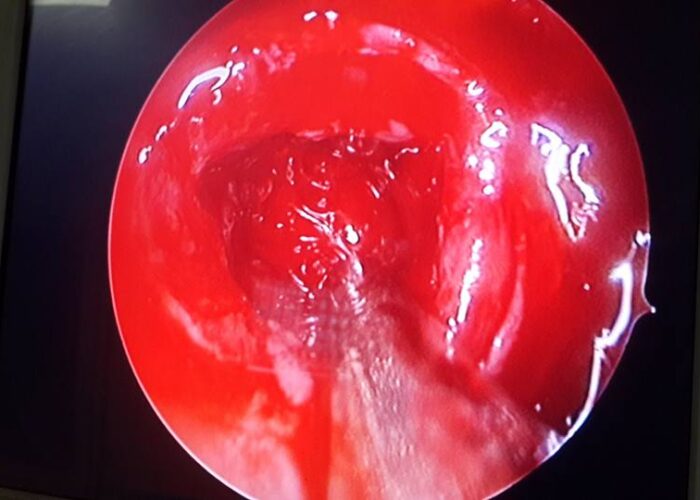

3 Endoscopic Pituitary Cases in Manik Hospital

Operated Case of Crico-Tracheal Anastomosis

Post Traumatic Tracheal Stenosis